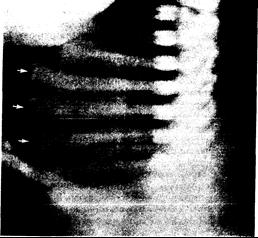

Рис. 339-1. Боковая рентгенограмма грудной клетки 9-месячного мальчика со «злокачественной» формой остеопетроза.

Следует обратить внимание на равномерное увеличение минеральной плотности тел позвонков и отчетливое расширение концов ребер (стрелки), указывающее на рахит.

При остеопетрозе угнетаются как образование, так и резорбция кости, но последняя — особенно сильно. Часто в костях имеются включения островков нерезорбированного кальцифицированного хряща. Нарушение реконструкции кости приводит к дезорганизации ее структуры с утолщением коркового слоя и сужением метафизарных каналов. Несмотря на повышенную плотность, кость становится неустойчивой к механическим воздействиям и легко ломается. Иногда компонентом остеопетроза у детей являются остеомаляция или рахит (рис. 339-1).